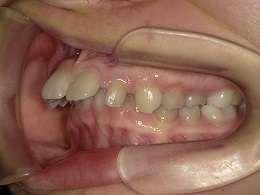

治療前左側

治療中左側

治療後左側

治療前右側

治療後右側

お試し矯正後、深い噛み合わせ改善のため上下全体矯正中の患者様の症例になります。